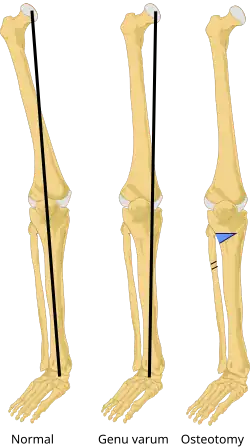

Genu varum (also called bow-leggedness, bandiness, bandy-leg, and tibia vara) is a varus deformity marked by (outward) bowing at the knee, which means that the lower leg is angled inward (medially) in relation to the thigh's axis, giving the limb overall the appearance of an archer's bow. Usually medial angulation of both lower limb bones (fibula and tibia) is involved.[1]

Treatment for children with Blount's disease is typically braces but surgery may also be necessary. In children guided growth surgery is used to gradually correct/straighten the bow legs.[13] For teenagers osteotomy or bone cutting is often used to correct the bone deformity. The operation consists of removing a piece of tibia, breaking the fibula and straightening out the bone; there is also a choice of elongating the legs. If not treated early enough, the condition worsens quickly.[14]